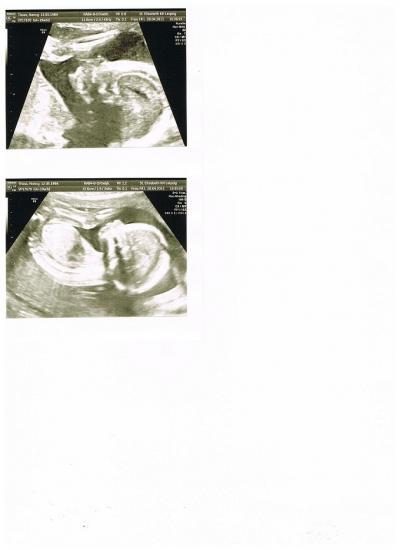

Guten Morgen Kimi, sorry das ich mich gestern nicht noch gemeldet habe. Mein Mann und ich sind nach der FD spontan ins Kino gefahren und haben den Kinostart von Fast&Furios five geschaut. Lies man meine letzten beiden Beiträge, da bist du auf dem Laufenden! Kurz und knapp: Wir bekommen nochmal einen kleinen Jungen, habe zwei US-bilder beigefügt, und er wird CHRISTIANO heißen! Er ist ca. 20 cm groß und völlig zeitgerecht entwickelt! Sind soooo happy!!!!! Leider stimmt die Lage meiner Planztra nicht und dies wird in am 29.06.2011 nochmal überprüft! Melde dich wenn du von deiner FD kommst, ist ja gerade soweit! Denke an dich!

Bild zu @sweetheart17 - Forum für September - Mamis